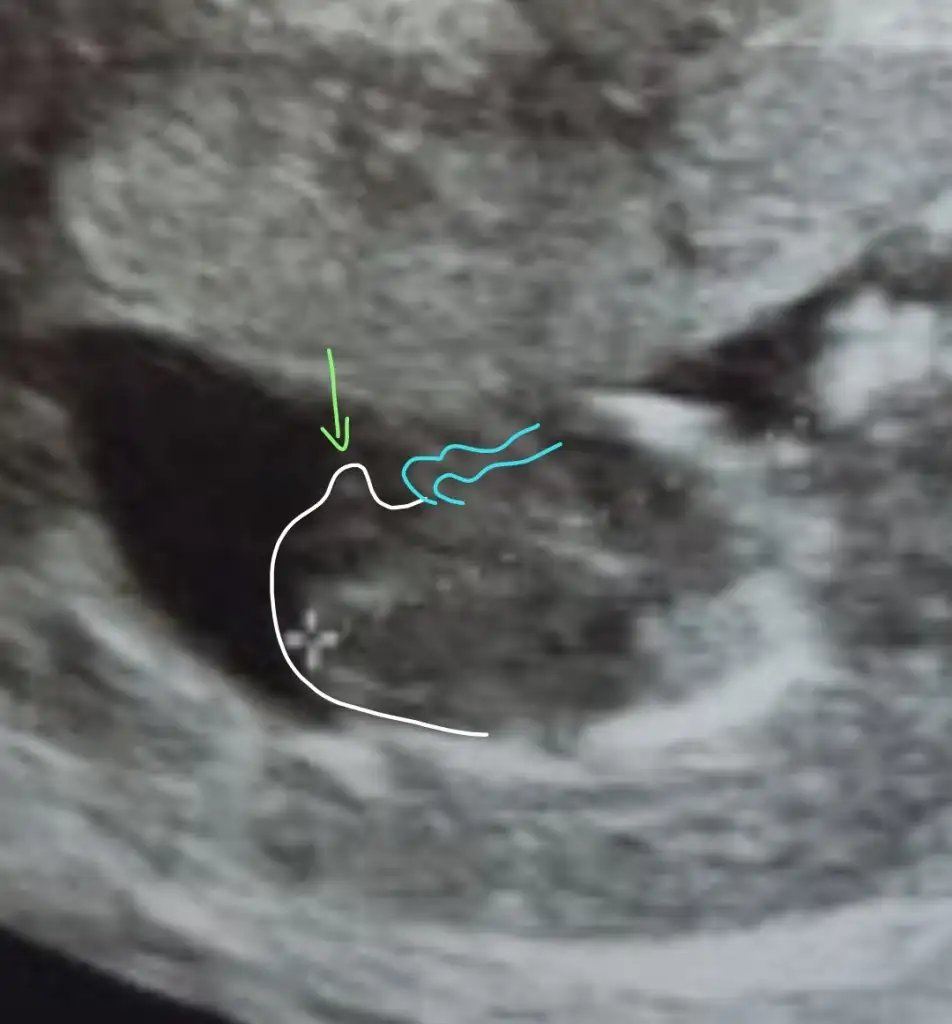

Merhaba Ikra meyra 'cım. Benim de 12+4 ultrason görüntüm. Bize de tahmin de bulunabilirsen çok mutlu olurum

Eklentiler

• 20210524_115115.webp

19,3 KB · Görüntüleme: 51

Kız sanki emin olamadım başka USG varsa paylaşın